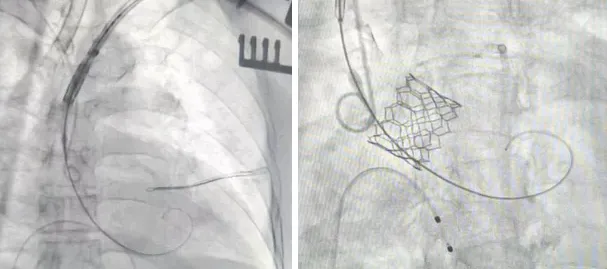

团队为患者实施了经腋动脉导管主动脉瓣置换术(TAVR)。患者是73岁男性,有陈旧性心肌梗死、心力衰竭、心脏骤停及心脏支架手术病史,因反复呼吸困难3年、近1个月加重至无法平卧,入住朝阳医院冠心病重症监护室(CCU)。检查显示患者心脏功能严重受损,主动脉瓣存在中重度狭窄与关闭不全,心脏扩大且泵血能力下降,还伴有肺动脉高压。患者符合TAVR手术条件,但术前发现下肢动脉病变严重,一侧血管闭塞、另一侧严重狭窄且钙化明显,无法通过常规的股动脉入路手术。经多学科讨论,决定改用非常规的腋动脉入路实施手术。在杂交手术室,血管外科副主任宋盛晗团队全力协助,心内科主任医师徐立带领结构性心脏病介入治疗团队,顺利经左侧腋动脉为患者置入瓣膜,术后复查无明显异常。患者当日便拔除气管插管,恢复情况良好,心脏功能明显改善,术后4天顺利出院。

经腋动脉导管主动脉瓣置换术(TAVR)患者相关影像